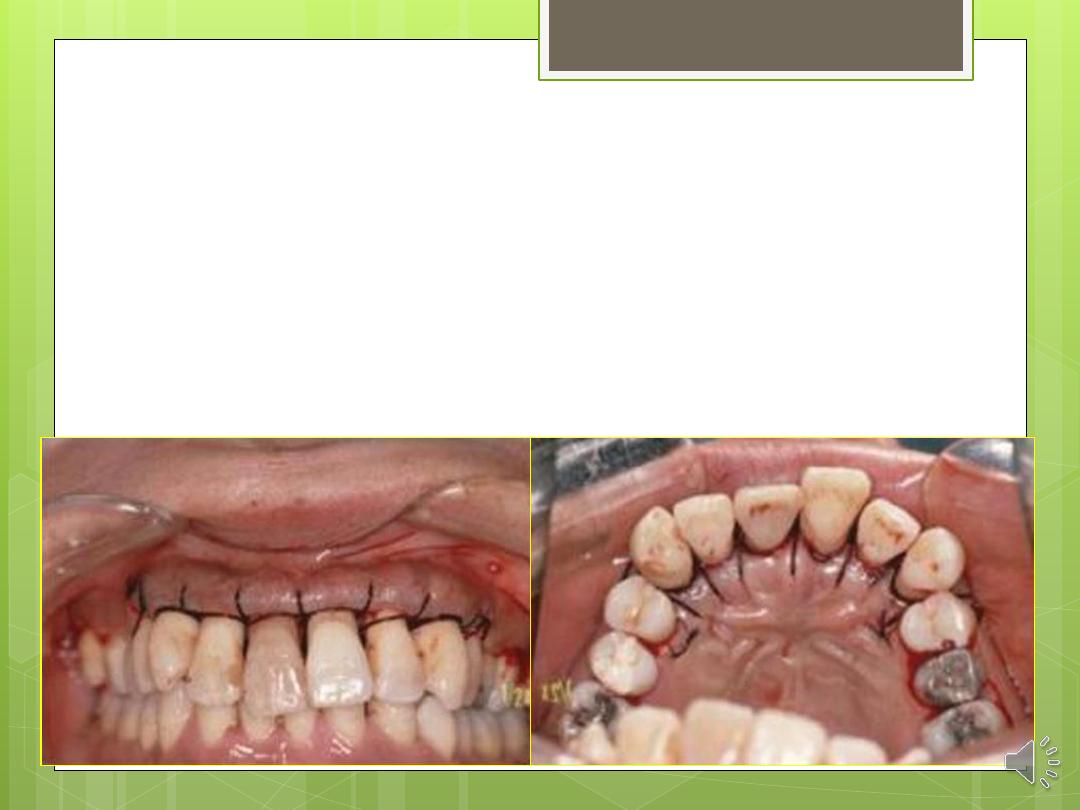

Step 7: The flaps are stabilized with sutures

and covered with a surgical dressing.